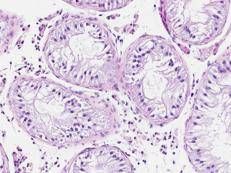

Sono oltre mille e hanno un ruolo cruciale nella regolazione dei geni e nel modo in cui gli organismi si sviluppano e funzionano

Il premio per la scoperta microRna e del suo ruolo nella regolazione genica